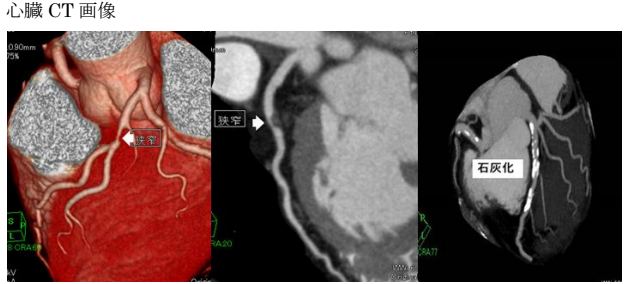

冠動脈CT(冠A-CT)検査について

当院では、冠動脈CT(冠A-CT)検査を行っております。

冠A-CT検査は、心臓の血管(冠動脈)をCTで詳しく調べる検査で、カテーテル検査の前段階として行える、体への負担が比較的少ない検査です。

冠動脈の狭窄(血管の狭くなり)や動脈硬化の状態を画像で確認することができ、自覚症状が出る前の早期の狭心症の発見や、将来の心筋梗塞のリスク評価(予知)に役立ちます。

胸痛・動悸・息切れなどの症状がある方はもちろん、 高血圧・糖尿病・脂質異常症がある方、健康診断で心疾患を指摘された方にも有用な検査です。

気になる症状がある方は、お気軽にご相談ください。

画像検査

X線CT装置で心臓を画像化するという試みは以前からありましたが、検査のためには息止め時間が最短でも40秒と非常に長く、患者さんに大きな負担を与えてきました。導入されているCT装置は、世界で初めて心臓の検査(120mmのスキャン範囲)を8秒の息止め時間で可能にした装置ですので患者さんの負担を大幅に軽減することが可能です。また立体像(3次元画像)として撮影部を360度自由な方向から観察することが可能です。

このX線CTを使用することにより、従来の画像診断装置では困難であった無症状の心血管の狭窄(きょうさく:せまくなっている)を早期に発見したり、カテーテル治療(細い管を体内に挿入し、その先端を風船状に膨らませて心血管の狭窄部分を広げたりする治療)のフォローアップ検査装置として期待されています。